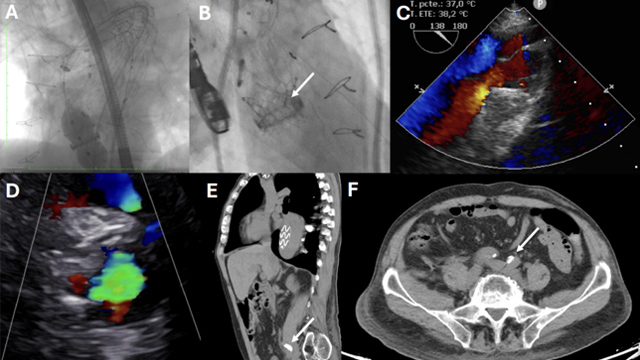

Emergency transcatheter valve interventions: alternative therapy or bridge to surgery?

16 Nov 2025 – From PCR London Valves 2025

This session offers a compelling case-based exploration of emergency transcatheter valve interventions, demonstrating their potential as life-saving alternatives or bridges to surgery in high-risk patients. Through detailed clinical scenarios including cardiogenic shock, acute papillary muscle rupture, and severe aortic regurgitation from infective endocarditis, participants gain practical...